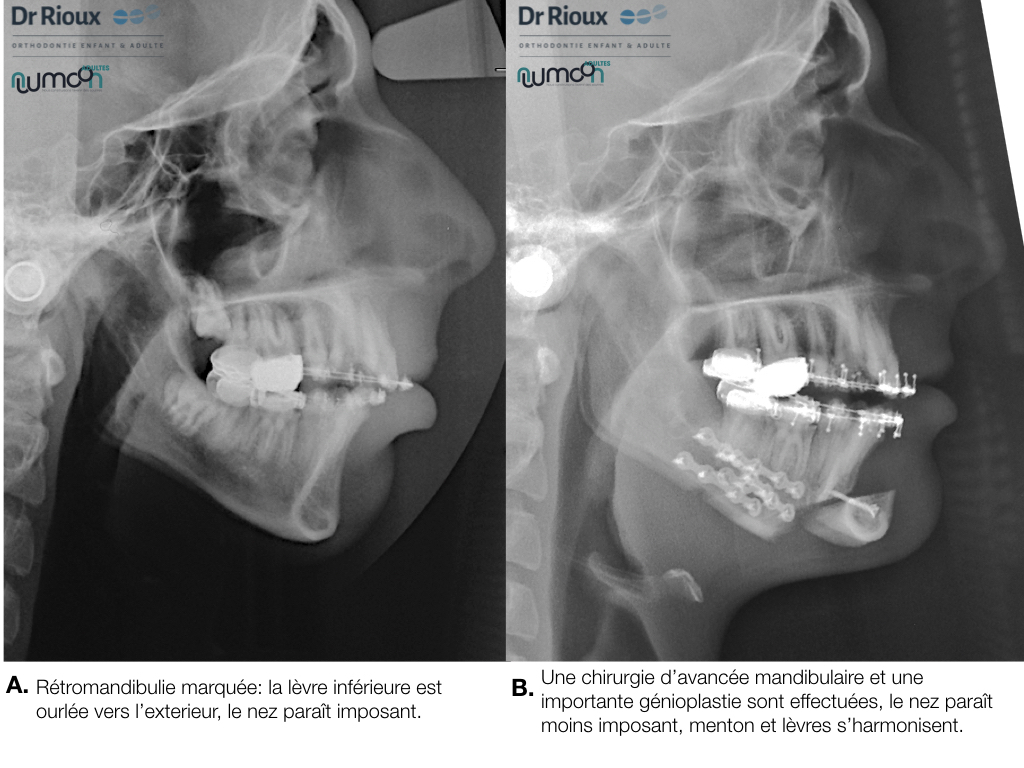

NUUMOON En images Arrêt des parafonctions (lolette, pouces, etc…) Orthodontie pédiatrique Orthopédie dento-faciale Apnée du sommeil de l’enfant (TROS) Esthétique du sourire Orthodontie et Articulation Temporo Mandibulaire (ATM) Traitement combiné ortho-chirurgicaux Traitements pluridisciplinaires Arrêt des parafonctions Effet de la lolette sur les dents Effet du pouce sur les dents Position de la langue et impact sur les dents Mieux respirer pour mieux grandir Respiration et santé Respiration et santé Sans titre.004 Orthodontie pédiatrique Conséquences ventilation orale – nuumoon ChatGPT Image 5 sept. 2025, 09_00_25 conséquences posturales de la ventilation orale Prévention canine incluse Prévention canine incluse Prévention canine incluse Dents qui s’emboitent à l’envers Dents qui s’emboitent à l’envers orthopédie dento-faciale Traitement déformation mâchoire Déformation des mâchoires : menton en avant Déformation des mâchoires : menton en avant Déformation machoire Déformation machoire Déformation machoire : machoire du bas en arrière Déformation des mâchoires : menton en avant Déformation des mâchoires : menton en avant Posture dents et mâchoire Anomalie de la mâchoire Apnée du sommeil orthodontie invisible à Genève Aligneurs transparents & bagues linguales – l’art de corriger sans rien laisser paraître Troubles de l’articulation temporo-mandibulaire et bruxisme Chirurgie orthognathique Traitements pluridisciplinaires INSIGHTS Contenu pour les enfants